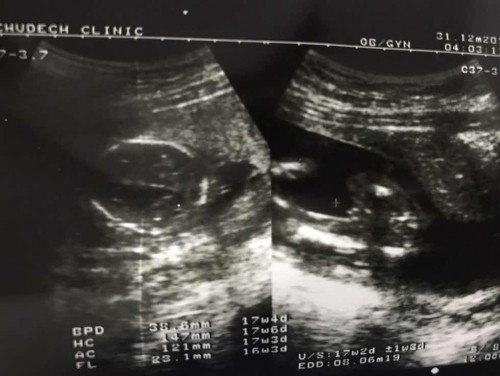

ขอเสียงคุณแม่เดือน มกราคม จ้า แม่บ้านนี้ได้ ผู้ชาย🤰🤰🤰👪